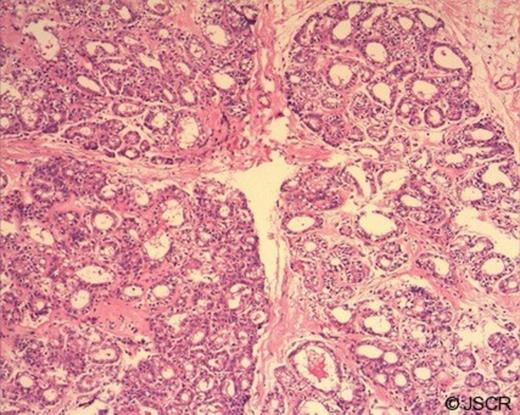

The external surface was lobulated and the cut surface was nodular with focal white areas. Representative samples were taken and routinely processed. Haematoxylin and eosin stained four-micron sections showed a well circumscribed tumor composed of hyperplastic acini retaining the configuration of normal breast lobules (Fig.2). There was no evidence of atypia or malignancy. There was stromal hyalinisation.

H&E, X 100. Hyperplastic acini retaining normal lobular configuration.